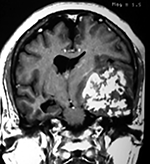

Paciente masculino de 34 años de edad, quien presenta crisis convulsivas parciales motoras de brazo y hemicara derecha, secundariamente generalizadas, posteriormente hemiparesia 4/5 para hemicuerpo derecho.

La TAC muestra un área hiperdensa a nivel frontal izquierdo heterogénea que no refuerza con medio de contraste.

LA RMN muestra una lesión bien circunscrita frontal parasagital izquierda con edema perilesional, hiperintensa en T1 y T2, de contenido sólido y quístico, con poca captación del medio de contraste.

Se realizó craneotomía frontal para abordaje interhemisférico anterior.

Se realiza resección total de la lesión de contenido hemático oscuro-verdoso, consistente en un angioma cavernoso. La RMN postoperatoria se observa solo la brecha quirúrgica sin evidencia de lesión.

En el postquirúrgico el paciente desarrollo síndrome frontal lateral, que se controló con Risperidona y remitió después de tres semanas, las crisis convulsivas remitieron y el medicamento se disminuyó de manera paulatina (figs. 4 y 5).

Figura 4:

Imágenes prequirúrgicas y postquirúrgicas de lesión multiloculada del caso 9.